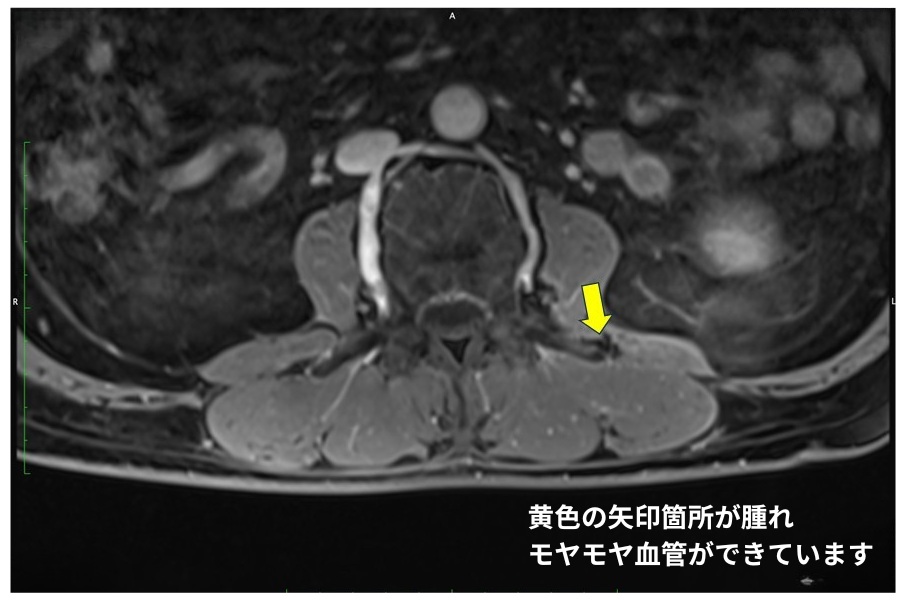

診察と併せて、痛みの本当の原因を特定するために「造影剤を使ったMRI検査」を行いました。一般的なレントゲンなどでは異常が見つかりにくいのですが、この特殊なMRIを撮ることで、隠れていた腰痛の原因がはっきりと見えてきます。

検査の結果、腰の骨同士を連結している「椎間関節(ついかんかんせつ)」の近くや、腰の外側寄りの筋膜に、痛みの原因となる「モヤモヤ血管(異常な新生血管)」が濃く写し出されました。

患者さんが「痛い」とおっしゃる場所と、この異常血管がある場所が完全に一致していました。 長年の中腰姿勢や、腰をひねる動作の繰り返しによって腰回りに過度な負担がかかり、その微細な損傷の修復過程で異常な血管と神経が一緒に増殖してしまい、それが長引く激痛の原因になっていたと考えられます。